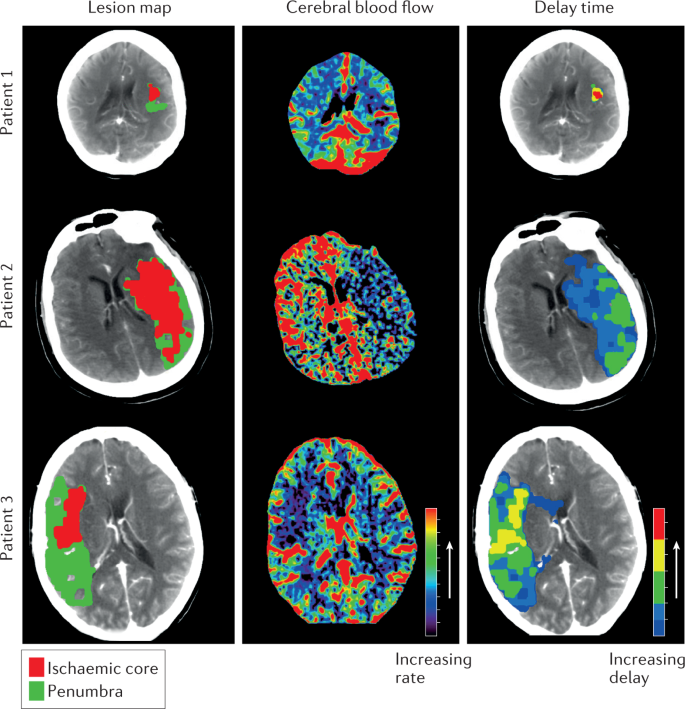

CT imaging, including noncontrast CT (NCCT), CT angiography (CTA), and CT perfusion (CTP), are the most often the initial imaging modalities in stroke evaluation . At our institution, NCCT followed by CTA is the initial study in stroke evaluation . CTP is performed in select cases to help stratify patients for treatment .

A comprehensive evaluation may be performed with a combination of computed tomography (CT) or magnetic resonance (MR) imaging techniques . Unenhanced CT can be performed quickly, can help identify early signs of stroke , and can help rule out hemorrhage .

Diffusion weighted imaging (DWI) is a commonly performed MRI sequence for evaluation of acute ischemic stroke , and is sensitive in the detection of small and early infarcts . Conventional MRI sequences (T1WI, T2WI) may not demonstrate an infarct for 6 hours, and small infarcts may be hard to appreciate on CT for days, especially without the benefit of prior imaging .